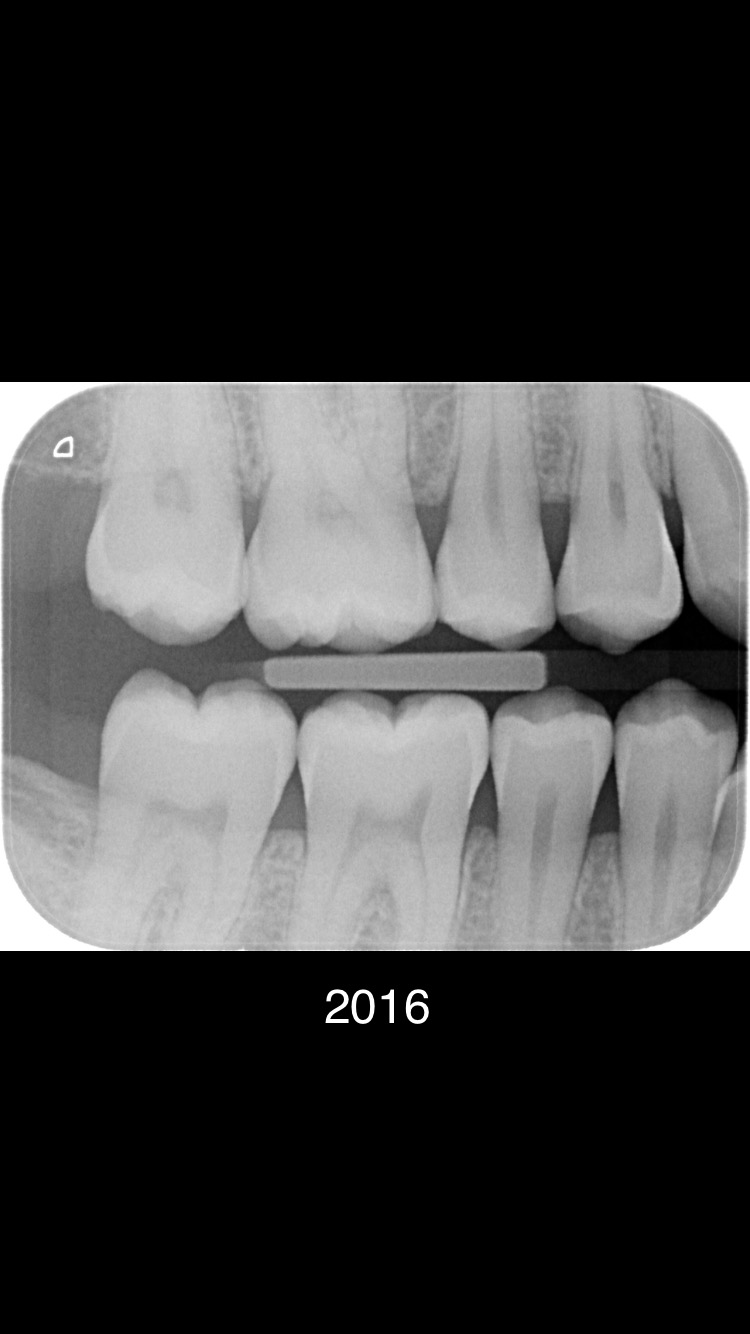

Er zijn meerdere beginnende plekjes maar die zijn nog niet door het glazuur dus hoeven nog niet aangepakt te worden. De vier in de linker boven en onderkaak gevonden "gaatjes" zou ik ook aanpakken. 25.26.35,36.......24 kan ik niet goed beoordelen dus twijfel.16 zou ik nog niet doen. In 2021 waren er links enige die net wel of net niet door het glazuur zijn.. dus ik kan begrijpen dat uw tandarts dat in de gaten heeft gehouden, gemonitord. Maar wat heeft u gedaan tussen 2020/2021 en 2023.. Gebruikt u wel ragers elke dag???>of andere reiniging hulpmiddelen voor tussen de tanden en kiezen. Let op uw voeding/drank gebruik... beperk het aantal invloed momenten op uw gebit tot 6. etc etc. dit gaat fout. Op de status praesens v uw gebit zie ik maar 5 aantekeningen niet 7. Maar ik ben niet goed in rekenen.

Helaas alle praktijken moeten verdienen... Het is een onderneming geen charitatieve instelling. Alle prijzen worden voor ons door NZA bepaald hebben wij niets over te zeggen. Lees mijn advies hierboven wat gaatjes betreft. Niet elke dag tussen alle tanden en kiezen een rager gebruiken vind ik zeer onverstandig. Zie alle defecten...zijn allemaal tussen de kiezen waar een tandenborstel niet maar een rager wel kan komen. Wanneer bent u voor het laatst bij de tandarts geweest??. Blijkbaar gaat er iets fout. Houdt bij zoals ik heb aangegeven en bespreek dat met de mondhygiënist. Laat ook daadwerkelijk zien hoe u reinigt er gaat iets fout. Dat v niet elke dag een rager gebruiken is er een. Als al beginnende "gaatjes" zijn niet elke 6 mnd naar de tandarts gaan is nr 2. Foto v 2021 was niet alarmerend maar toen is iets fout gegaan. Dus in twee jaar tijd.

Je gaat toch niet zelf de gaatjes vullen ??.Heeft u mijn verbaasde vraag hierboven gelezen of u een rager gebruikt. Ik ben blij als mijn cliënten 2xdgs een rager gebruiken, minimaal 1xpd.n Het gaat om de meest recente foto. De oude foto's geven een beeld v progressie v defecten.